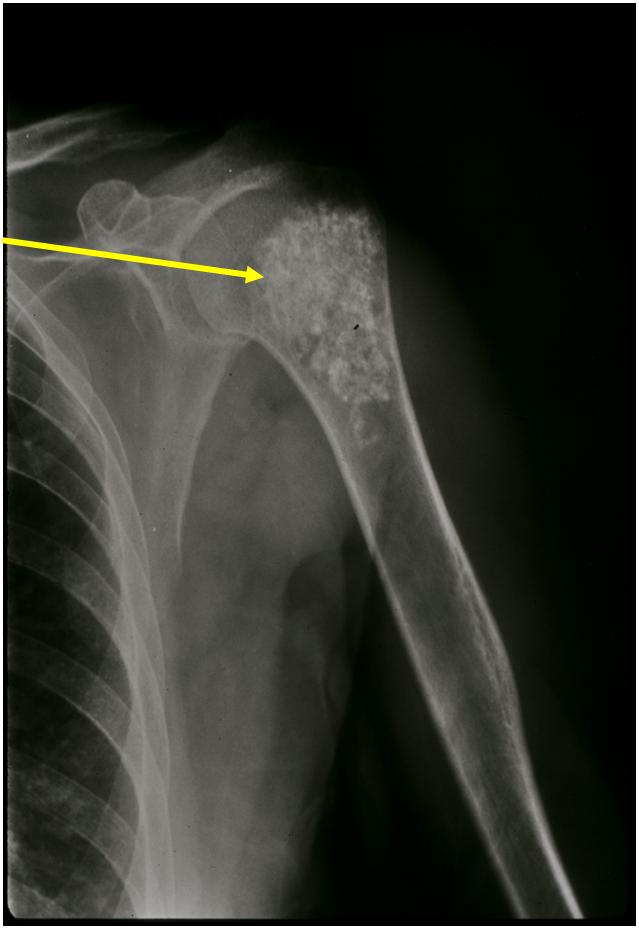

- Localized, radiolucent defect usually with punctate calcifications

- Calcifications are typical but not always present

- Matrix may demonstrate various degrees of calcification

- Calcifications are stippled, punctate, popcorn like calcifications and “Ring and Arc” calcifications

- Cartilage tumors grow in a lobular manner. The perimeters of the lobules undergo

- enchondral ossification that may calcify. If the entire perimeter of the lobule calcifies it appears

- radiographically as a “Ring”. If a portion of the perimeter of a lobule calcifies it forms an “Arc” on

- an X-ray.

Plain X-Ray:

- Geographic lytic lesion

- Central often metaphyseal in long bones

- Can be eccentric also

- Expansile remodeling with thinned cortex

- Chondroid matrix with calcifications in majority of tumors

- Approximately 20% have limited or no calcifications